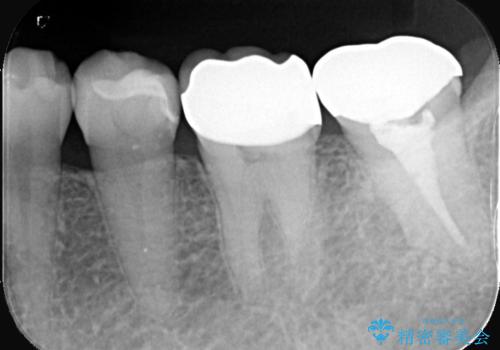

- 銀歯の下の虫歯です。お写真で分かるように広範囲で深い虫歯でした。

1歯はオールセラミッククラウンもう1歯はセラミックインレーで治療を行いました。

かなり虫歯が大きく深かったですが、神経は取らずに残す事が出来ました。